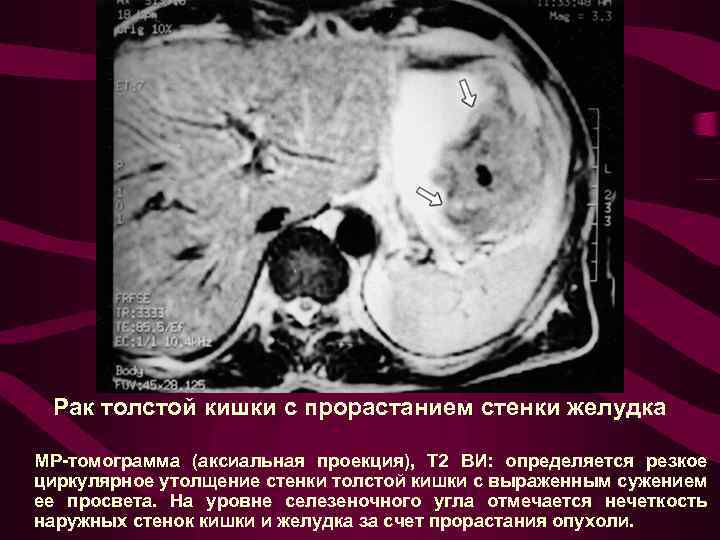

Рак толстой кишки с прорастанием стенки желудка МР-томограмма (аксиальная проекция), Т 2 ВИ: определяется резкое циркулярное утолщение стенки толстой кишки с выраженным сужением ее просвета. На уровне селезеночного угла отмечается нечеткость наружных стенок кишки и желудка за счет прорастания опухоли.